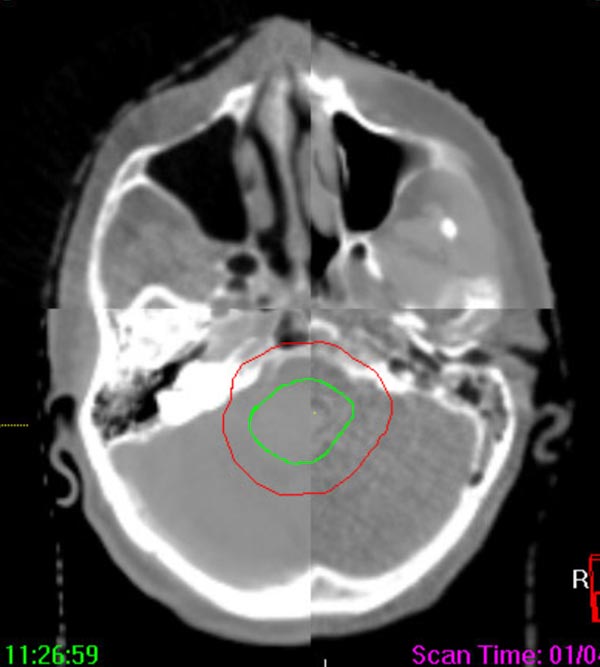

The 3-D high-quality images taken at the time of your treatment can be studied against your previous CT scans precisely and promptly to ensure that the doctors are treating your tumor as accurately as possible while greatly limiting any exposure to healthy tissue in the area.

Elekta Synergy® provides unparalleled clinical assurance to more aggressively treat tumors while keeping damage to surrounding healthy tissues to a minimum. Elekta Synergy®‘s precision accuracy reduces or eliminates the use of markers because clinicians can view soft tissue using Elekta Synergy®‘s VolumeViewTM. The low-dose imaging proficiency helps minimize the side effects of radiation therapy by decreasing the margins previously set to account for the unpredictability of target location, movement, and dimensions.